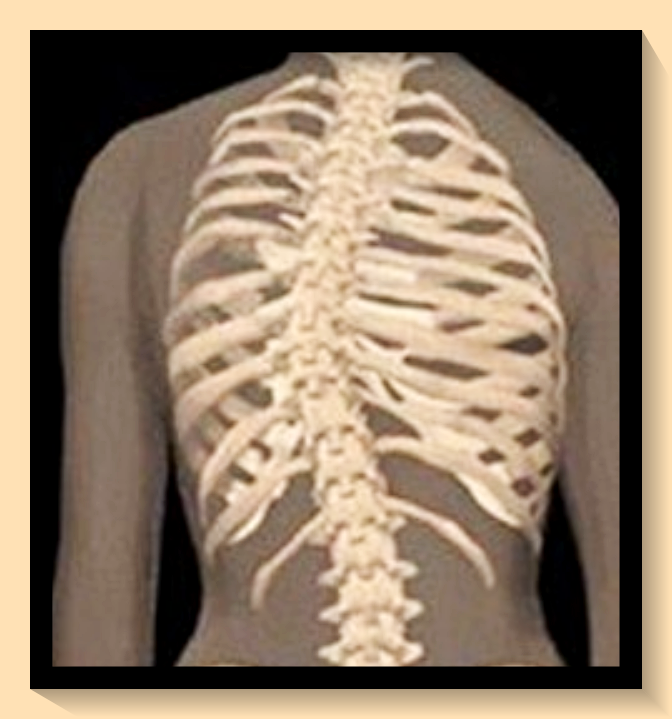

척추측만증이란 척추가 곧게 서 있지 않고 한 쪽으로 휘어져 있는 상태를 지칭하는데요, 이는 우리가 생각하는 것보다 더 심각한 건강 문제를 야기할 수 있습니다. 척추의 변형이 심해질수록 주변 장기에 압박이 가해져 기능 장애가 발생할 수 있답니다.

척추측만증의 주요 증상으로는 상체의 기울어짐, 어깨 높이의 차이, 허리 통증, 비정상적인 걸음걸이 등이 있습니다. 더 심한 경우에는 심장과 폐에 문제가 생길 수도 있어요.